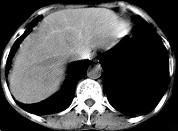

问题 男,40岁有血吸虫感染史,腹胀不适,食欲减退,CT扫描所见如图,最可能的诊断是 ( )

选项 A.肝炎后肝硬化 B.血吸虫后肝硬化 C.酒精性肝硬化 D.胆汁性肝硬化 E.脂肪肝

答案 B